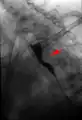

Aberrant subclavian artery at axial CT-scan. (1) trachea, (2) esophagus, (3) Aberrant subclavian artery. Aberrant right subclavian artery at angiography.

Aberrant right subclavian artery at angiography. Tape-like impression of the esophagus caused by aberrant subclavian artery. Below (arrows) narrowing of the esophagus by a tumor that is causing the swallowing problems.